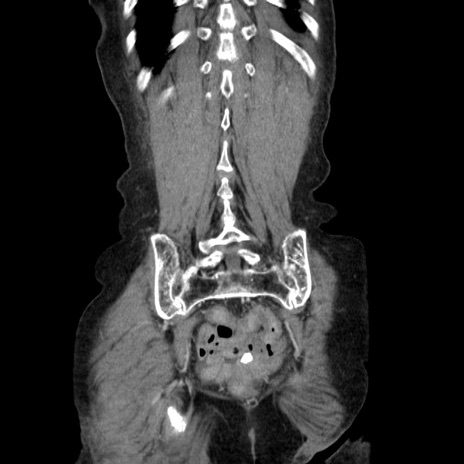

症例25(冠状断像)

【症例】80歳代女性

【主訴】胸のつかえ感

【現病歴】約9時間前に食後から胸のつかえた感じあり、嘔吐あり、来院。

【既往歴】胃癌(全摘)、胆摘、虫垂炎

【身体所見】心窩部に圧痛あり、反跳痛なし。

【データ】WBC 5700、CRP 0.05